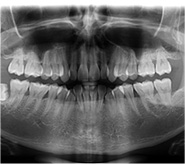

初診檢查拍片費用